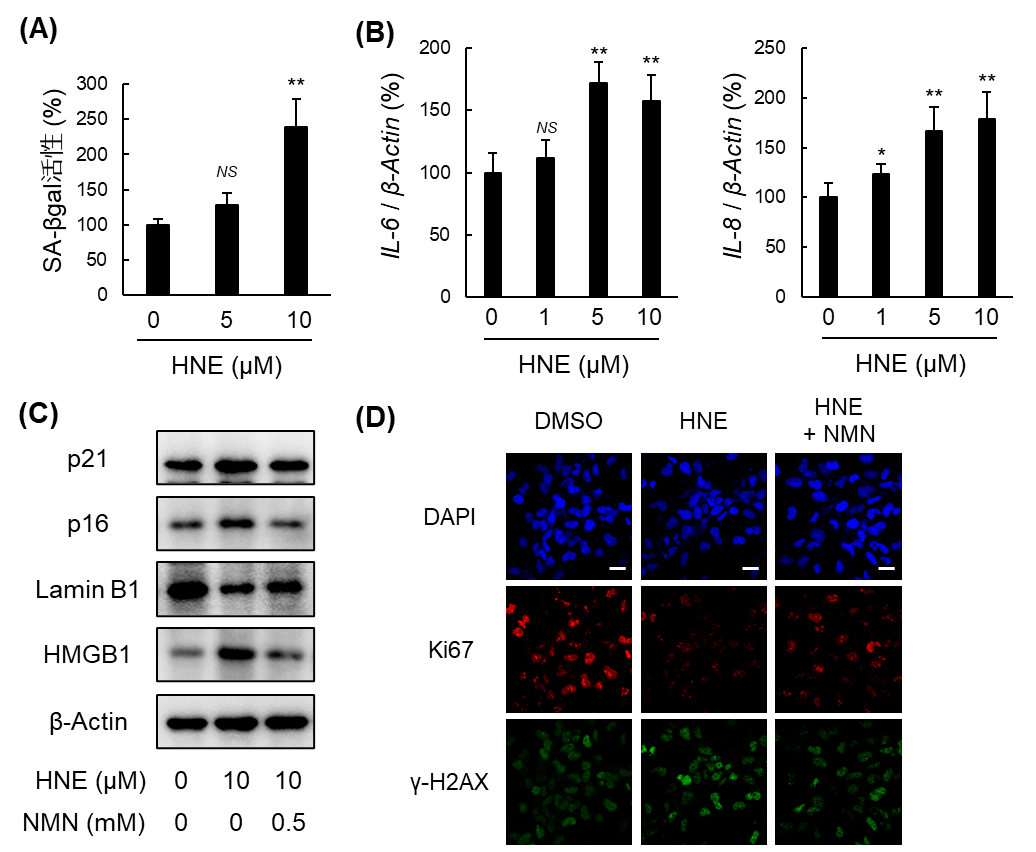

本研究では、脂質過酸化由来の有害なアルデヒドであるHNEおよびその酸化体4-オキソノネナールが、ヒト肝星細胞株LX-2において細胞老化を誘導することを明らかにしました。これらのアルデヒドに曝露された細胞では、細胞老化指標であるSA-βGal活性の上昇に加え、細胞周期停止因子(p21、p16)や細胞老化関連分泌表現型(SASP)因子の発現増加が確認されました。また、核膜を構成するラミンB1の消失やDNA損傷マーカーの増加も観察され、酸化ストレスが肝星細胞の正常な機能を失わせ、炎症や線維化を促進する「老化状態」へと変質させることが明らかになりました。

図1. HNE誘導性細胞老化に対するNMNの抑制効果

(A) SA-βgal活性. (B) SASP因子のmRNA発現. (C) 細胞老化関連因子のタンパク質発現. (D) 増殖マーカーとDNA損傷マーカーの発現